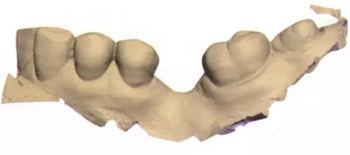

3b:無牙區(qū)的表面掃描

圖3c:表面掃描之后左側(cè)下頜骨區(qū)的重建圖

圖3d:在最大交錯位數(shù)字化重建牙弓

在此次就診中,也用TRIOS掃描儀(3Shape;圖2與圖3b-d)掃描左側(cè)上下頜骨和上下牙弓并進行咬合重建。只要把所有的診斷信息收集起來,第二天就可以復(fù)診治療。